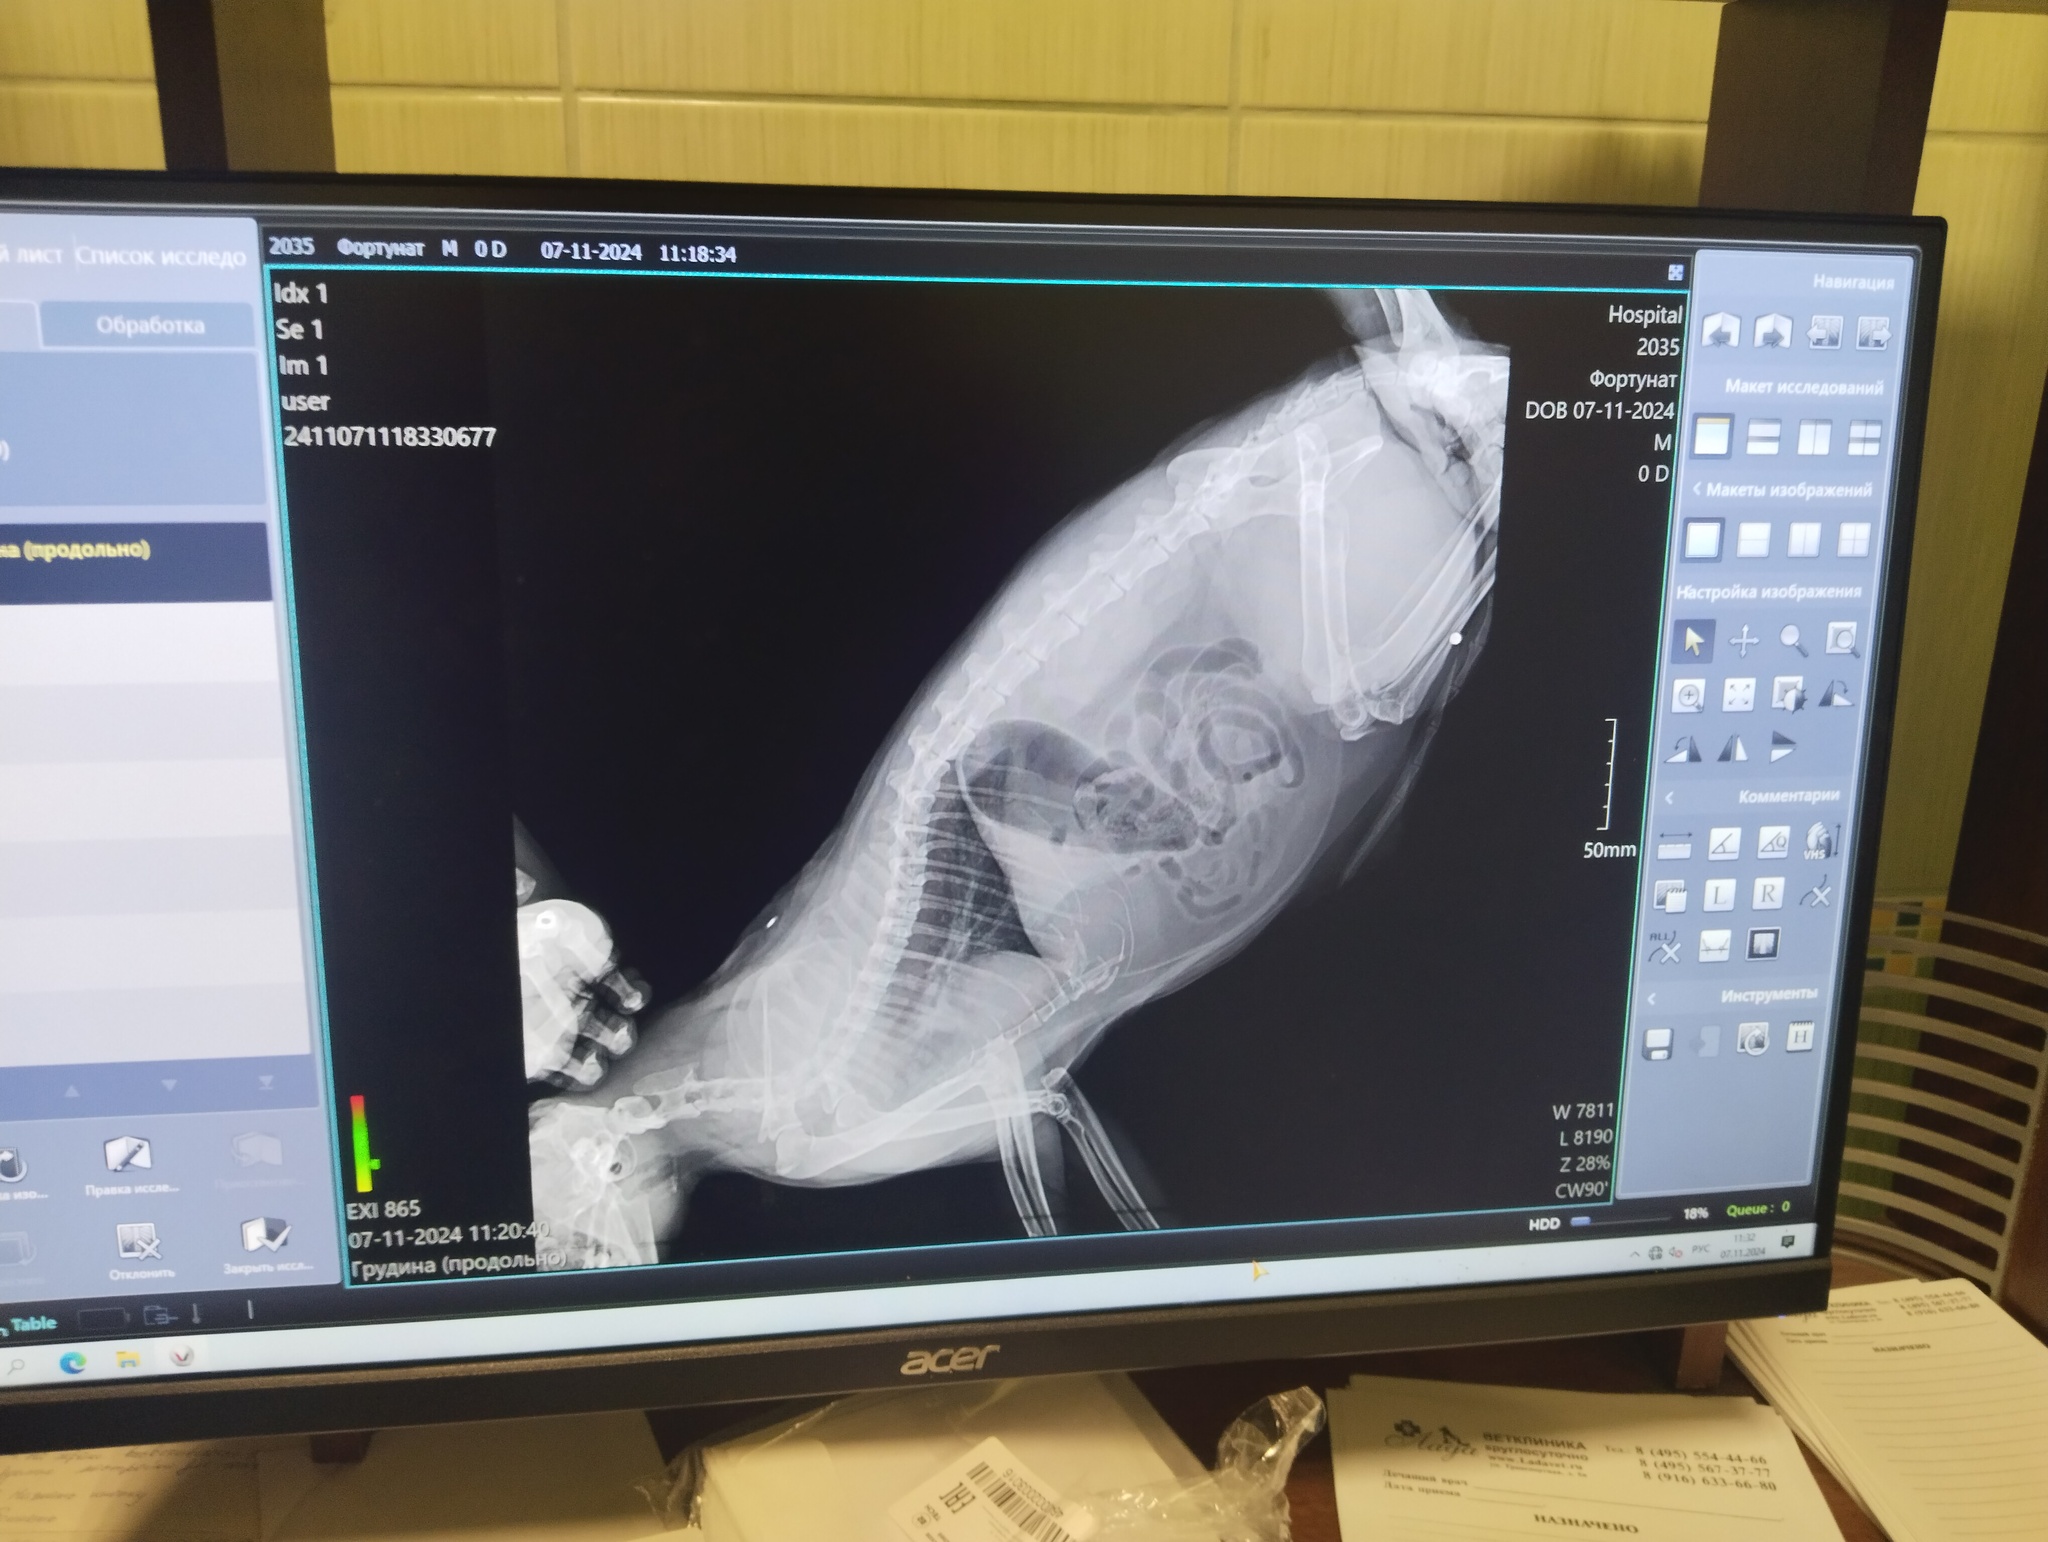

Мой котик про которого я писала ранее, заболел. Болеет тяжело. Обследование, анализы, исследования. Какого было удивление, когда сделали рентген.

Это пуля. Кот жил возле помойки в Люберцах, очень боится мужчин. Получается какой-то пидорас на улице стрелял из травмата в кота, относительно недавно +-5 лет. Какой нужно быть мразью так поступать.